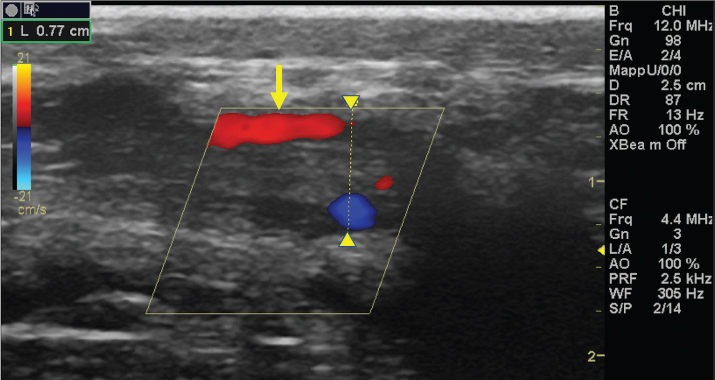

The left jugular vein appeared as an anechoic tubular structure which collapsed under the probe pressure, the color Doppler examination revealed normal blood flow within the vessel (Fig. 3). Bi-dimensional ultrasonography of the right jugular vein showed a heterogeneous, non-cavitating, hypoechoic structure occluding a narrowed right jugular vein for about 30 cm of length localized in the proximal and mid-portion of the neck compatible with a thrombus (Fig. 4). The color Doppler examination showed blood flow through the lateral portions of the thrombus in the cranial and mid-portions of the right jugular vein (Fig. 5). Cranially to the thrombus, a marked distension of the maxillary and linguofacial veins was evident, with a turbulent and echogenic flow; the latter was compatible with blood stasis near the thrombus (Fig. 6). Caudally to the thrombus, the right jugular vein presented reduced diameter, thickened walls, and normal blood flow (Fig. 7). The cranial part of the thrombus originated from a heterogeneous scare tissue, localized at the level of the right mandibular angle (Fig. 8). After injection of the first saline contrast bolus in a right facial vein, no microbubbles appeared in the right jugular vein, caudally to the thrombus, proving the presence of a complete right jugular vein occlusion. On the contrary, after injection of the second bolus, microbubbles were visualized in the left jugular vein as small, intense, echo signals within the vein lumen, demonstrating the presence of collateral circulation that drained the blood from the right facial veins to the left jugular vein (Fig. 9). Venography results confirmed the complete occlusion of the right jugular vein and the presence of submandibular venous collaterals that connected the right facial veins with the left jugular vein (Figs. 10 and 11). Based on the previous results, the diagnosis of JVT with complete occlusion of the vessel lumen was confirmed. The horse’s owner refused any proposed medical or surgical therapy.

Fig. 5. Color Doppler examination of the occluded right jugular vein in longitudinal section (between arrowheads). The image shows the presence of blood flow in the periphery of the thrombus (arrow).